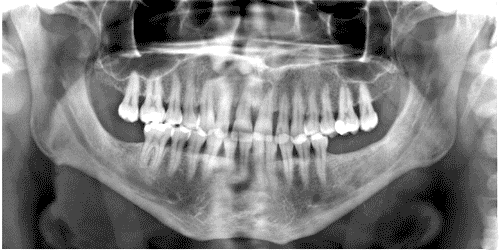

Panoramic images provide a useful overview of the teeth and jaws. They are commonly used for orthodontic surveys, to assess impacted teeth, and in implant planning

Panoramic images for the developing dentition show the presence and location of teeth